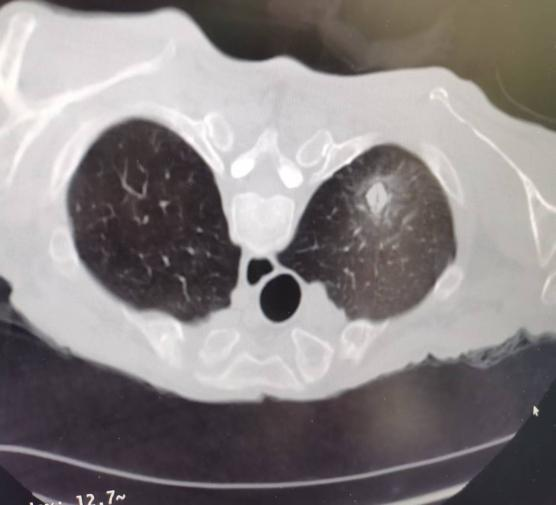

术前

张大爷因消化系统疾患就诊于我院,在后续进一步检查中,发现肺部存在高危结节,考虑为早期肺癌。由于患者高龄,心肺功能差,且合并多种慢性基础疾病,传统手术创伤大、风险高使家属和患者一度束手无策,治疗陷入困境。经我院肿瘤科团队综合评估患者身体状况、肿瘤位置及大小,最终确定采用CT引导下肺结节活检+同步射频消融的个体化治疗方案。